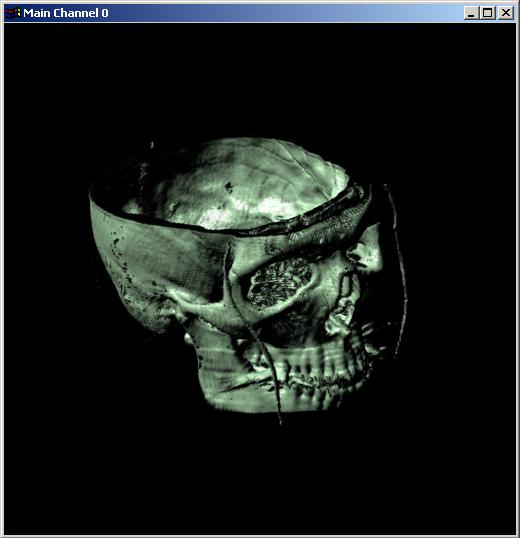

Visible human male CT data

Bone only

Data Resolution : 256x256x128

Visible human male CT data

Bone only

Data Resolution : 256x256x128

The following 12

images was generated by PC which has NVIDIA's GeForce3 GPU graphics card. The

hardware accelerated rendering techniques are used to make the following images.

To use the GeForce3 hardware, we have to use the OpenGL extensions like

GL_NV_texture_shader2, GL_NV_register_combiners, GL_EXT_texture3D,

GL_EXT_paletted_texture, GL_ARB_multitexture and so on. Since the GeForce3 card

allows the 3D texture shading, the image quality is better than the pixel of

frame buffer based shading in showing two materials at the same time.